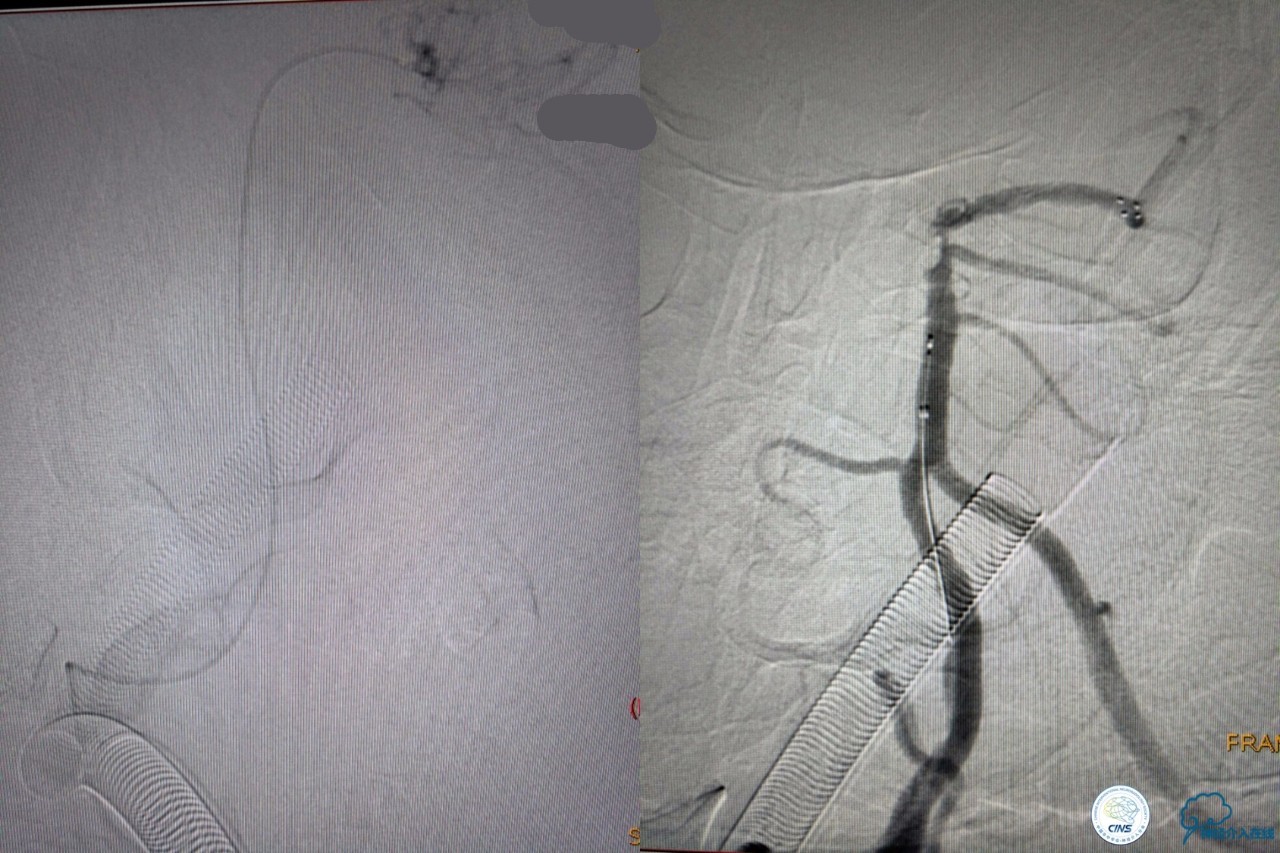

决定导管内给予替罗非班6ml,复查造影BA顶端仍闭塞,第二次取栓。

第二次取栓后可见基底动脉顶端仍有大量血栓,右侧大脑后动脉开通,但左侧大脑后未见显影且左侧小脑上动脉闭塞!

第三次取栓,支架放入左侧大脑后取栓。